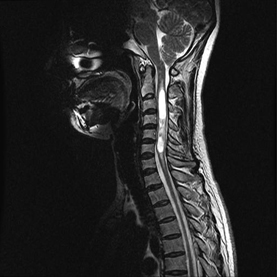

과거에는 척수 조영술, 척수 공동 조영술, 전산화 단층 척수 조영술 등이 사용되었으나, 최근에는 자기공명영상(MRI)이 가장 정확한 검사로 사용된다. 자기공명영상으로 척수공동의 존재 여부와 그 크기, 형태를 확인할 수 있으며, 척수 공동증의 원인이 될 수 있는 척수 종양과 같은 다른 척수의 상태도 알 수 있다. 척수에 대한 자기공명영상(MRI) 촬영이 가장 중요한 검사이며, 동반된 다른 중추신경계 질환의 판별을 위해 뇌에 대해서 추가적으로 검사를 할 수도 있다. 추가적으로 환자의 증상과 MRI에서 보이는 이상 사이에 관계가 있는지 감별하고, 신경의 신호 전도 속도 및 신호 강도 등을 평가하여 이상의 정도를 정량화할 수 있는 근전도 검사, 신경전도 검사 및 유발전위 검사를 시행할 수도 있으며, 경우에 따라서 뇌척수액 검사를 시행할 수도 있다.

경추에 발생한 척수 공동증 MRI: 척수 내에 하얗게 보이는 것이 뇌척수액이 고여 형성한 수종임